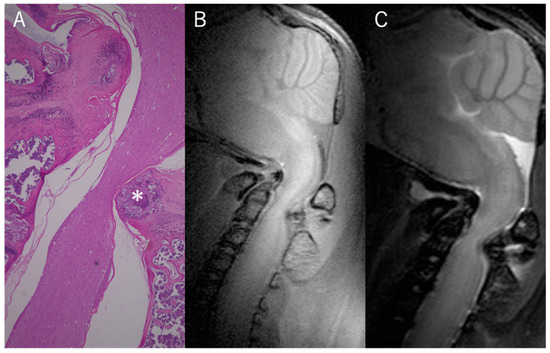

To account for magnetization transfer (MT) effects, the pulse was placed outside the brain region rather than without the labeling pulse. In the case of the labeling pulse used outside the brain region, the specific placement was decided carefully to ensure that it did not intersect with any region where CSF flow could be expected. The pulse was positioned in an area that was sufficiently far from the brain and the spinal cord to avoid any accidental labeling of the CSF. To guarantee this, the labeling pulse was placed at an area above the cranium, in the air, where we could be confident that no CSF flow is present. The labeling pulse for the fourth ventricle was placed in a section perpendicular to the midsagittal section (Figure 1). The rostral–caudal angle was defined as a line perpendicular from the dorsal apex of the fourth ventricle to the ventral side. The thickness of the labeling pulse was kept constant at 0.3 mm. We saved all image data as DICOM (Digital Imaging and Communications in Medicine) files and exported them to OsiriX (Pixmeo, Geneva, Switzerland) for analysis.

Figure 1. Sagittal slice of in vivo MRI mouse brain image. Labeling pulse for fourth ventricle (V4) was placed in section perpendicular to midsagittal section.